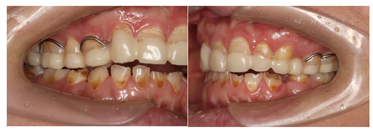

(1)面部检查:面部外形不对称,颏部居中,两侧口角高度不一致,面下1/3高度减小,两侧颧弓突度一致,下颌前突。中位笑线,上唇长度适中(图1)。(2)关节检查:颞颌关节:弹响(-),杂音(-),疼痛(-)。开口度正常,开口型有偏斜,肌肉触诊压痛:右侧上颌结节(+)、左侧上颌结节(++)、双侧翼内肌(+),其他肌肉及颞下颌关节区未诉异常,关节载荷实验无任何紧张和疼痛不适。(3)口内检查:上下颌牙中线较面中线向右偏斜,前后牙广泛不均匀磨耗,前牙磨耗后呈刃状;14、21、22、23及下颌牙唇颊侧颈部见釉质缺损,部分牙本质暴露,呈黄褐色,少量白垩色;44牙见开髓孔,表面暂封。12缺失,缺失牙间隙无。全口牙龈色形质未见异常,11牙、21牙唇侧牙龈龈缘高度不一致,21牙较11牙龈缘高约3mm。全口口腔卫生状况良好,菌斑、软垢少量,未及牙石及牙周袋。咬合检查:11-14牙与对颌牙反

,21牙与31、31牙对刃,左侧尖牙至前磨牙深覆盖,

曲线不平(图2,图3)。(4)影像学检查: